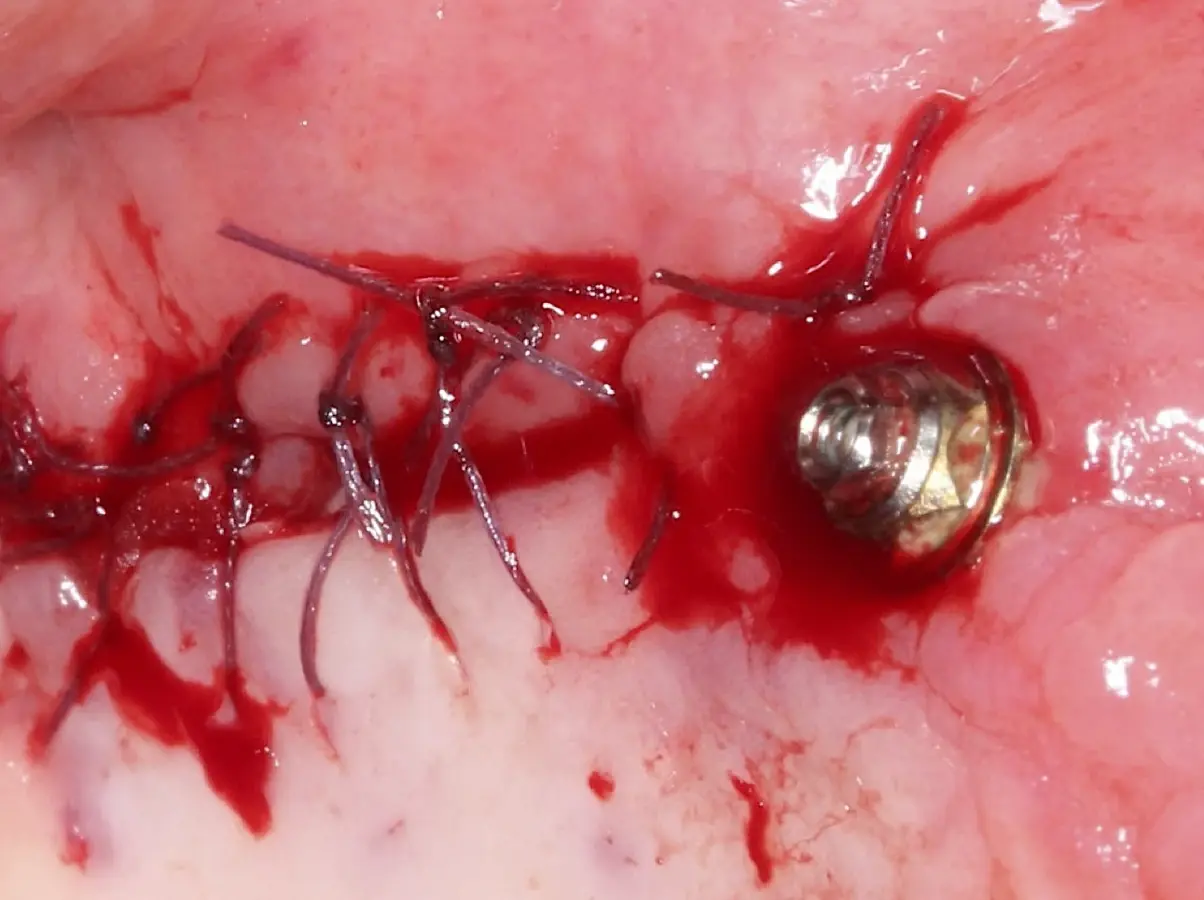

El tipo de inserto a ser utilizado dependerá del espesor de la pared ósea. Si la pared es menor a 0.5 mm, es mejor utilizar insertos de desgaste para prevenir la ruptura de la membrana de Schneider; si el espesor es mayor a 0.5 mm, se puede utilizar insertos de corte de espesor medio (Figura 3).